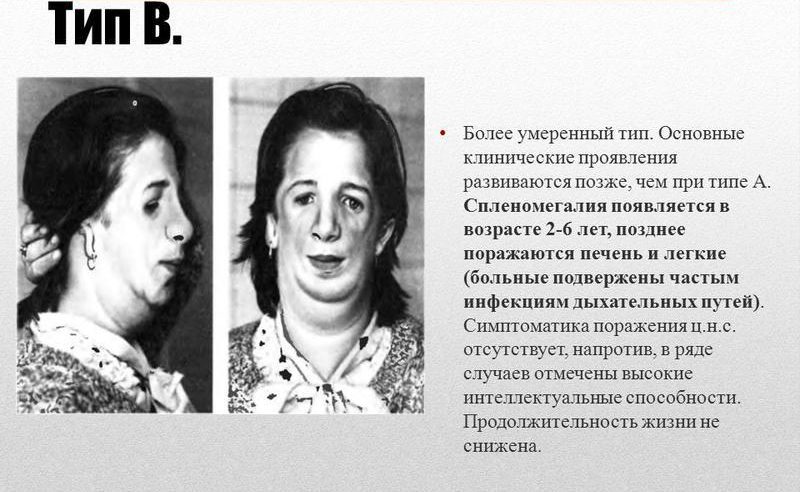

Болезнь Нимана-Пика Тип А: Симптомы и лечение

Раздел: Визуальный дайджест